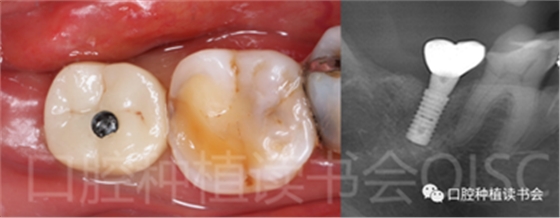

5.4.1 術后第8周,47取種植開窗式印模,O-Bite記錄咬合關系(圖23)。

5.4.2 47選擇原廠CAD/CAM基臺+ 愛爾創(chuàng)“魅影”全鋯冠,口外粘接為一體冠(圖24)。(義齒加工單位:哈爾濱芽美美牙工作室)

5.4.3 術后第10周,47戴入最終種植冠,X片確認基臺就位準確(圖25),以30N.cm扭矩旋緊基臺螺絲(圖26)。

5.4.4 種植冠封閉螺絲孔后,調(diào)合,拋光,完成最終修復(圖27);戴牙前CBCT顯示:種植體頰側(cè)骨板厚度為2.88mm;47種植冠獲得了良好的穿齦輪廓,并維持了正常的頰側(cè)牙弓輪廓。